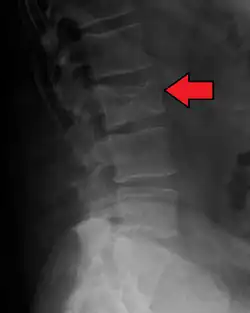

-

Pathological fracture of the lumbar spine due to multiple myeloma -